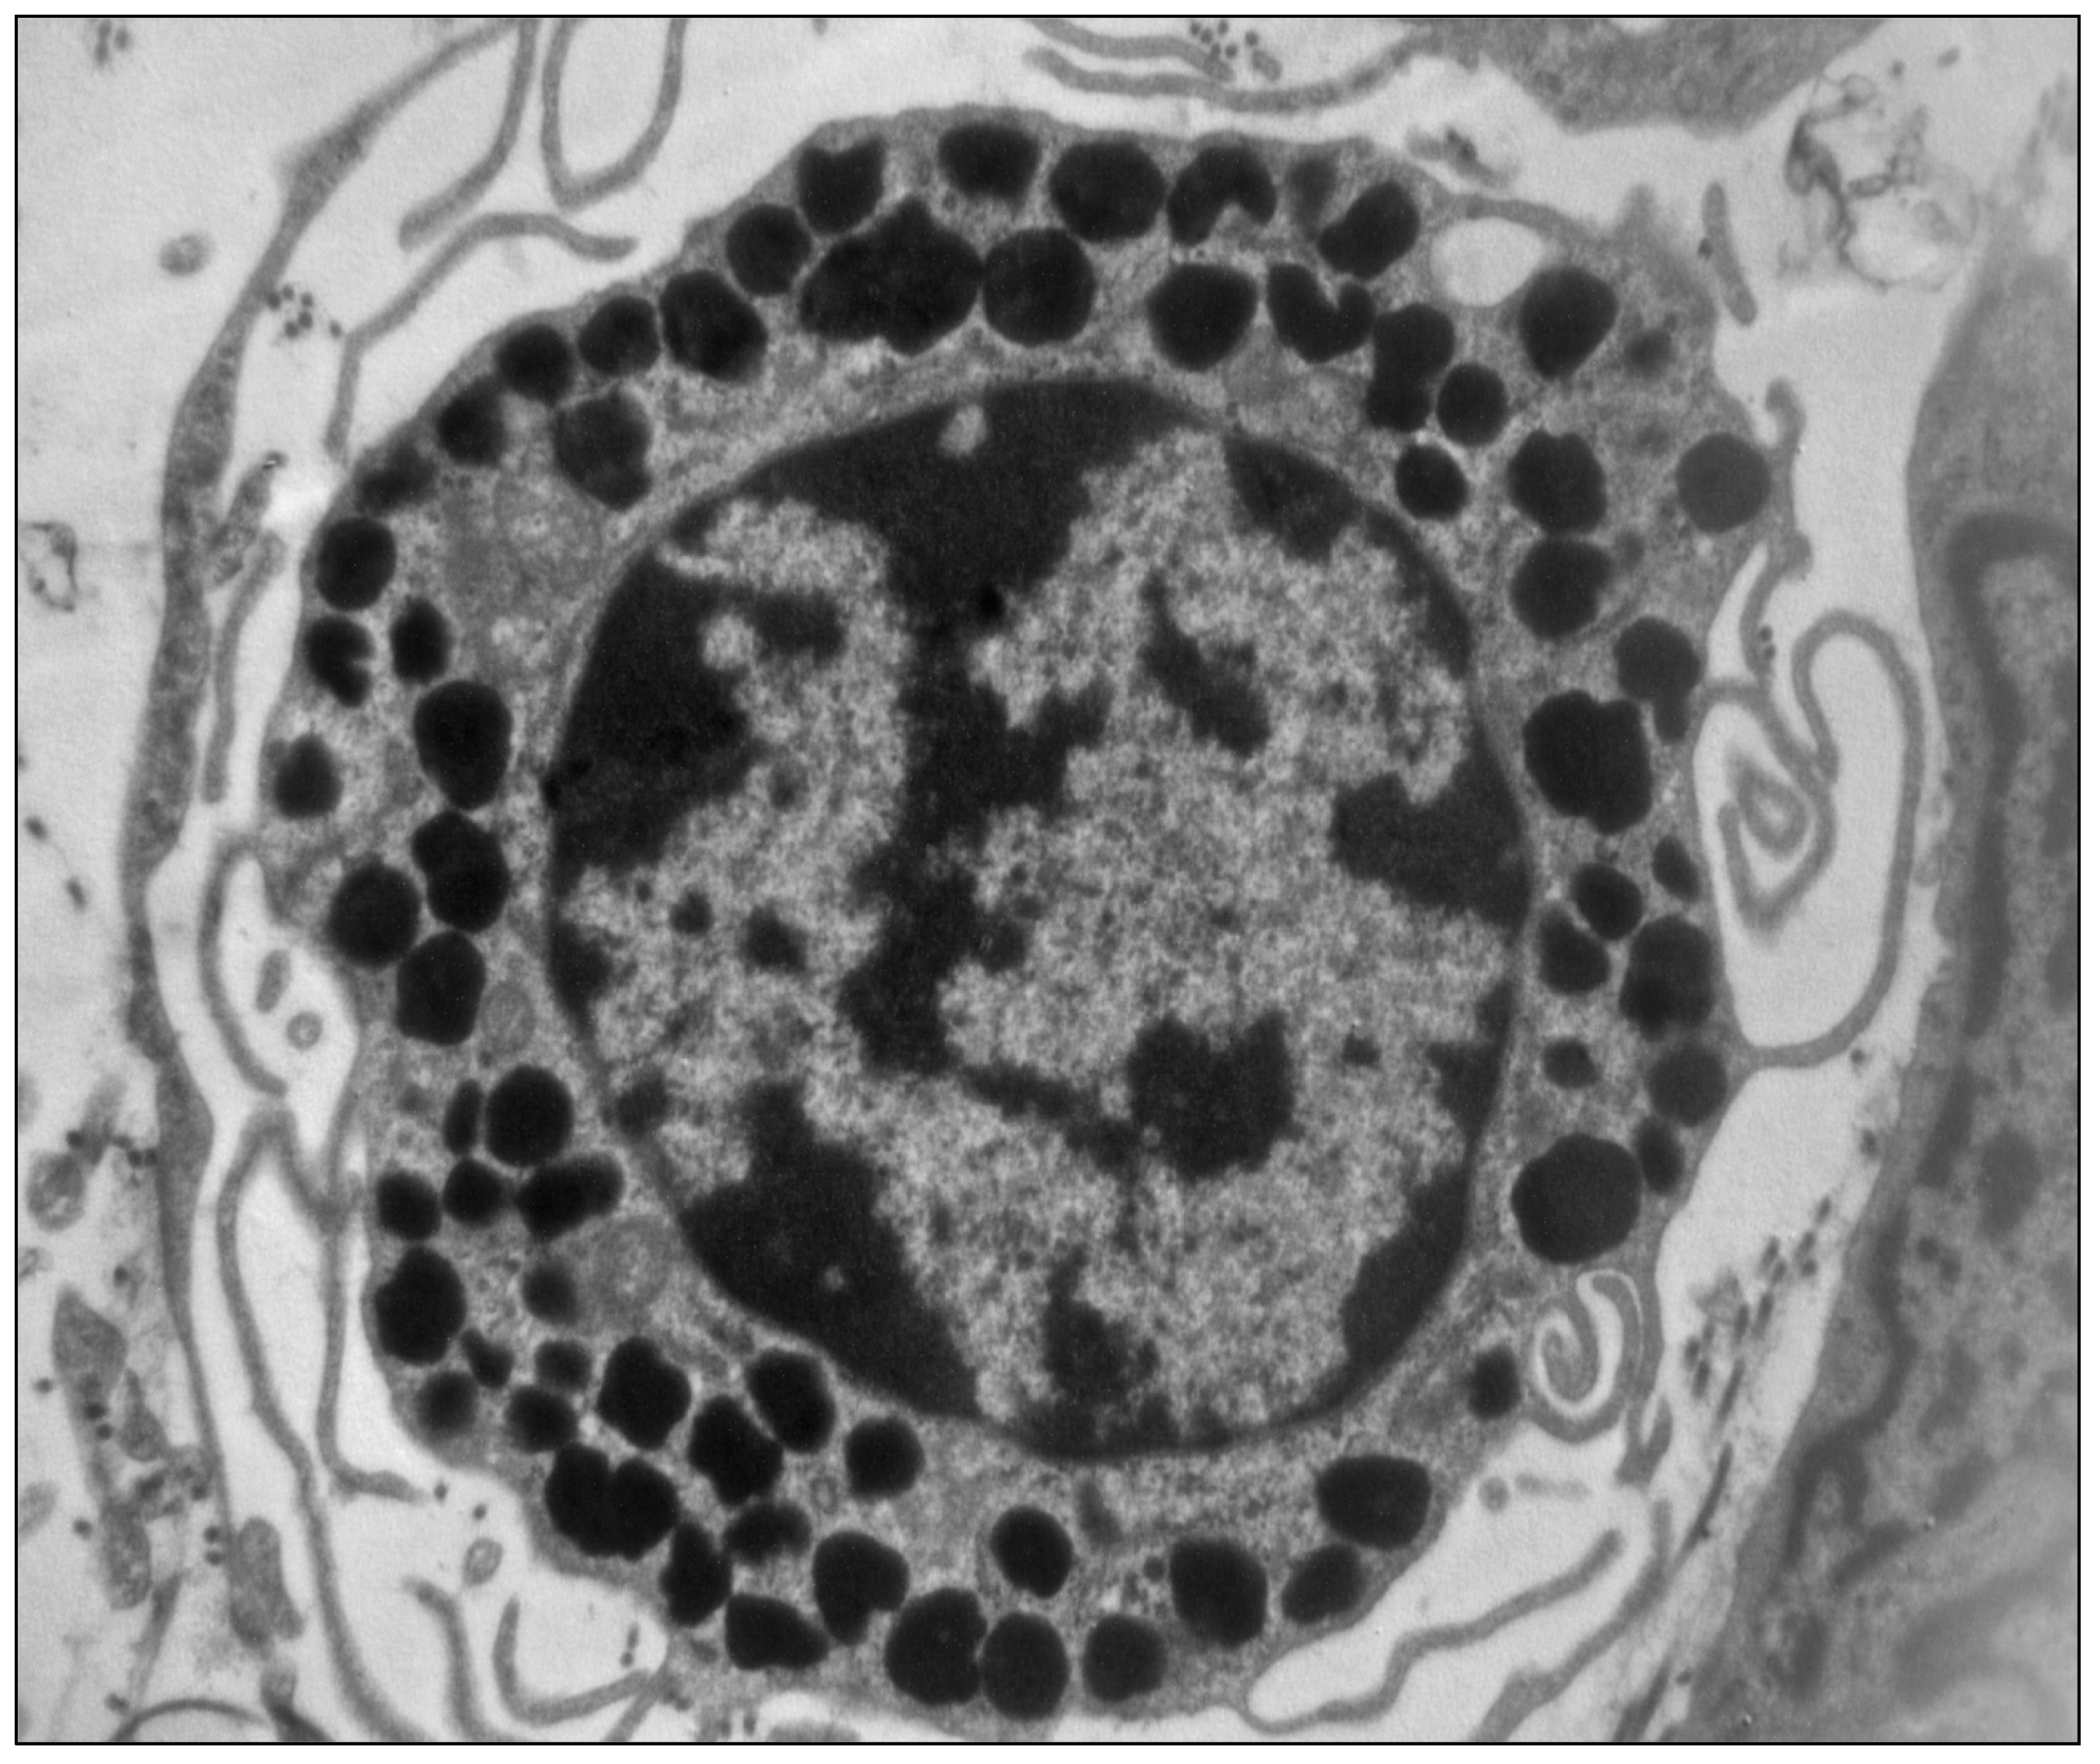

- Martino, L.; Masini, M.; Bugliani, M.; Marselli, L.; Suleiman, M.; Boggi, U.; Nogueira, T.C.; Filipponi, F.; Occhipinti, M.; Campani, D.; et al. Mast cells infiltrate pancreatic islets in human type 1 diabetes. Diabetologia 2015, 58, 2554–2562. [Google Scholar] [CrossRef] [PubMed] [Green Version]

- De Boer, P.; Pirozzi, N.M.; Wolters, A.H.G.; Kuipers, J.; Kusmartseva, I.; Atkinson, M.A.; Campbell-Thompson, M.; Giepmans, B.N.G. Large-scale electron microscopy database for human type 1 diabetes. Nat. Commun. 2020, 11, 2475. [Google Scholar] [CrossRef]